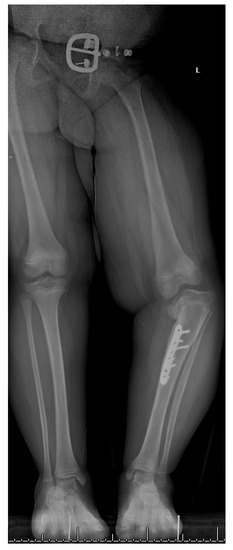

17. Gradual Correction with External Fixation

18. Late-Onset Tibia Vara (LOTV)